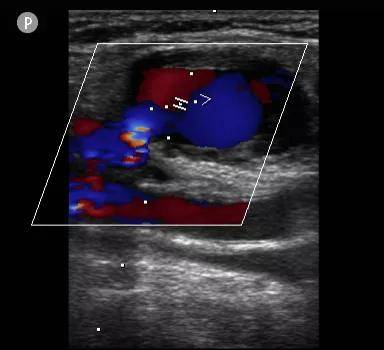

凝血酶注射前:右侧腹股沟区假性动脉瘤形成 , 其内可见红、蓝色血流信号 。